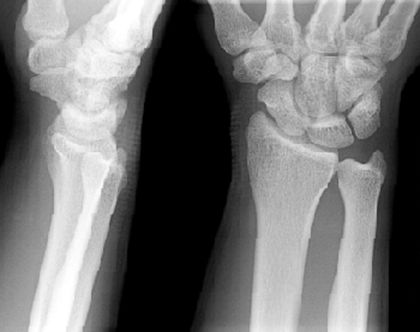

正常腕关节

疼痛科怎么理疗疼痛科医生、康复理疗科医生、针刀针灸医生应掌握的常见骨科疾病X光片_https://www.jmylbn.com_新闻资讯_第23张

疼痛科怎么理疗疼痛科医生、康复理疗科医生、针刀针灸医生应掌握的常见骨科疾病X光片_https://www.jmylbn.com_新闻资讯_第24张

月骨周围脱位

疼痛科怎么理疗疼痛科医生、康复理疗科医生、针刀针灸医生应掌握的常见骨科疾病X光片_https://www.jmylbn.com_新闻资讯_第25张